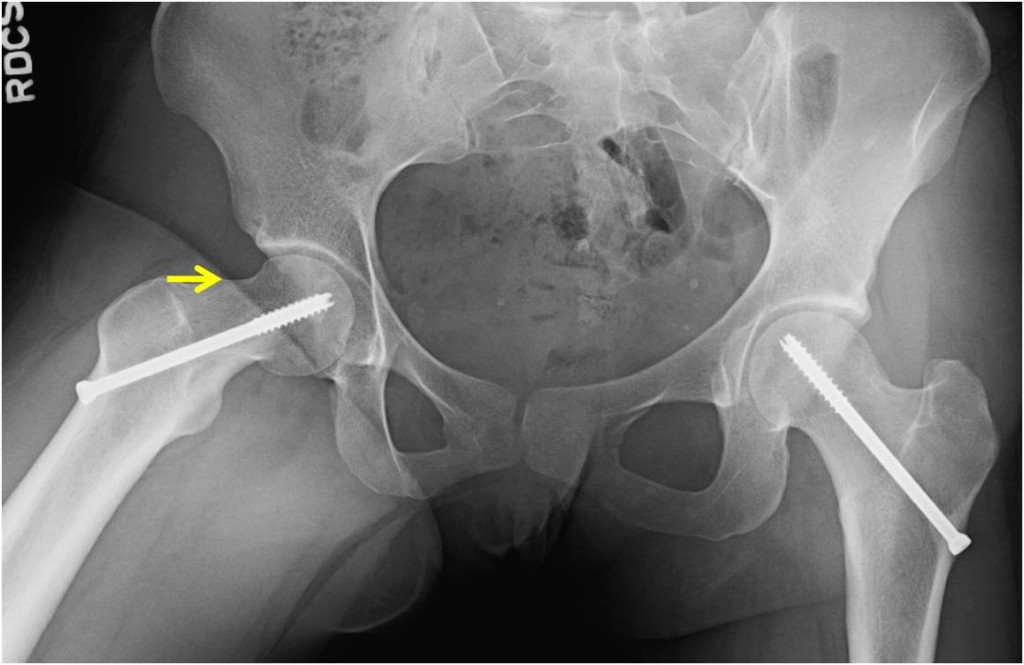

Slipped Upper Femoral Epiphysis – Radiology Cases

epiphysis femoral upper slipped pelvis radiology surgical radiograph intervention radiologycases

Slipped Upper Femoral Epiphysis – Radiology Cases

femoral epiphysis upper slipped radiology radiologycases pelvis